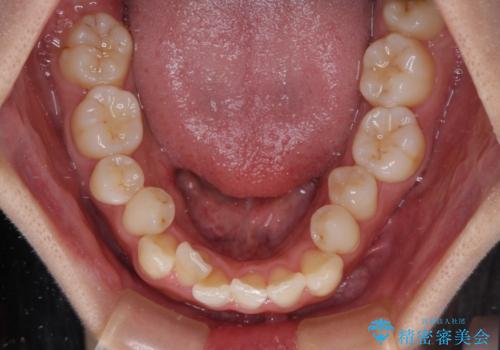

- 上下前歯のデコボコを気にして来院された患者様です。

上顎歯列が下顎の歯列に対して狭小であり、一部下顎の奥歯が上顎よりも外側に位置している状態でした。

上顎の急速拡大装置を使用して上顎骨を側方に拡大することで上顎歯列を拡大し、下顎歯列も拡大できるようにすることで、歯列を整えることとしました。